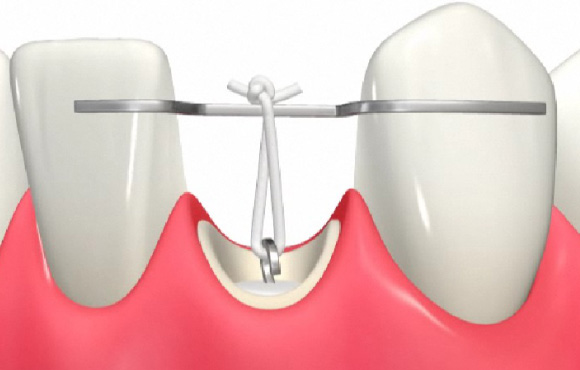

挺出処置(エクストルージョン)

虫歯が深くこのままでは冠が入れられません。

ゴムで引っ張り上げることで歯茎の中から歯の健全な部分を露出させ被せ物で処置することが可能になります。

①歯が深くこのままでは適切に被せ物ができません。ゴムで歯歯茎の中に埋まっている健全な歯質を出してきています。

②二か月ほどでゴムの力をかけ2mmから3mm牽引しました。

③引っ張り上げたことで歯茎の位置も変化するため適切な位置に歯茎を移動させるための歯周外科処置を行います。

④被せ物ができるだけの十分な歯質を得ることができました。

⑤その後、ハイブリッドクラウンで被せ物をセットしました。